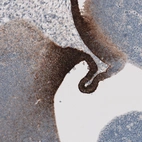

Immunohistochemical staining of human liver shows moderate to strong membranous positivity in hepatocytes.